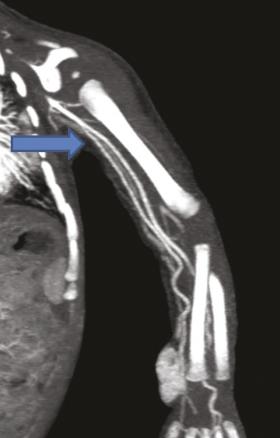

Ce nourrisson de 11 mois était hospitalisé pour l’exploration d’une masse à l’extrémité inférieure de l’avant-bras. À l’échographie, on notait une formation tissulaire hypervasculaire au Doppler couleur, motivant un complément d’investigations. L’imagerie par résonance magnétique étant techniquement difficile à réaliser, un angioscanner a été demandé, qui montrait (fig. 1 et 2 ) une tumeur vasculaire à développement essentiellement sous-cutané respectant les structures musculaires et osseuses. Il mettait en évidence une variante anatomique : une origine haute de l’artère radiale sans cross-over avec l’artère cubitale.